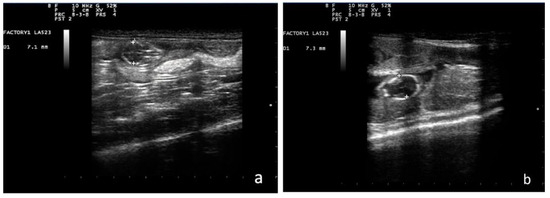

Prediction of Parturition in Ferrets Using Ultrasonographic Fetal Measurements

The gestation period in ferrets lasts 42 days (range 38–42). Numerous cases of maternal and paternal cannibalism have been reported, so it is important for breeders to know the exact date of parturition in order to separate the mother from the other ferrets [...] Read more.

The gestation period in ferrets lasts 42 days (range 38–42). Numerous cases of maternal and paternal cannibalism have been reported, so it is important for breeders to know the exact date of parturition in order to separate the mother from the other ferrets in the herd. Fetal ultrasonographic biometry and specific formulae for assessing fetal growth have not yet been developed in ferrets as they have been in dogs and cats. The aim of this study was to develop a formula, similar to those available for other domestic species, that could be used in ferrets to date the birth of a litter to within one day. Among the different ultrasonographic parameters, the biparietal diameter (BP) gave a very accurate prediction and showed a significant relationship with days before parturition. The formula developed could allow better planning of care before, during and after parturition, thus helping to reduce neonatal mortality. Full article